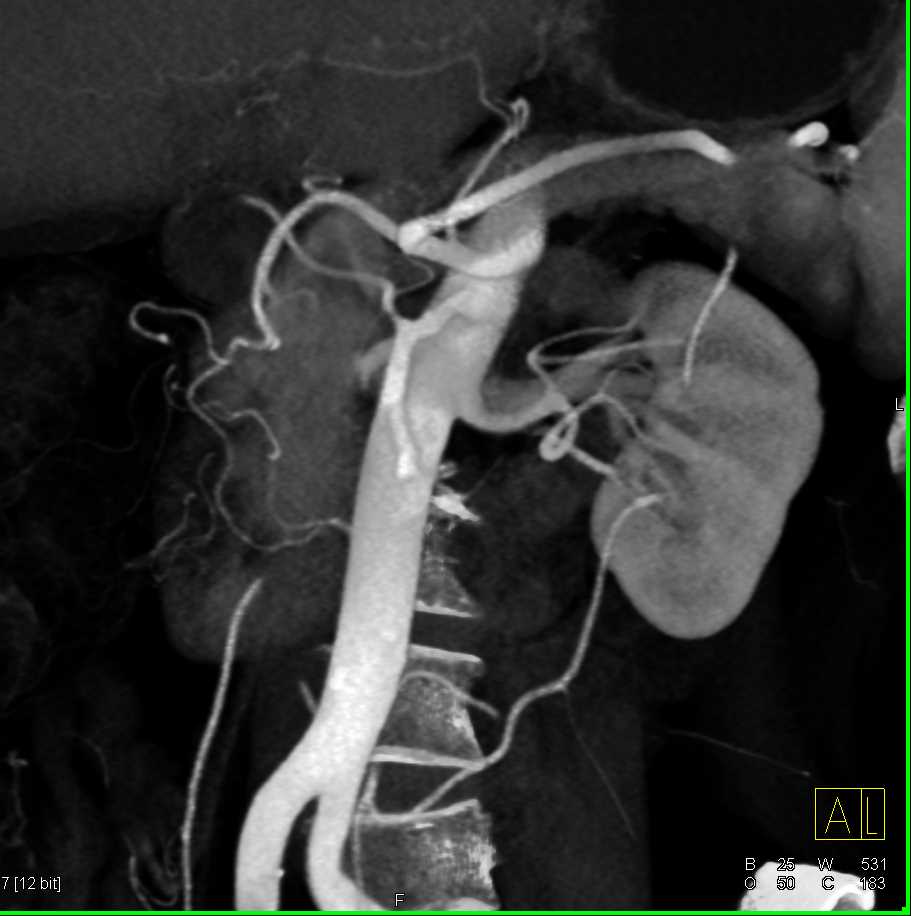

Neuroendocrine Tumor Body of Pancreas